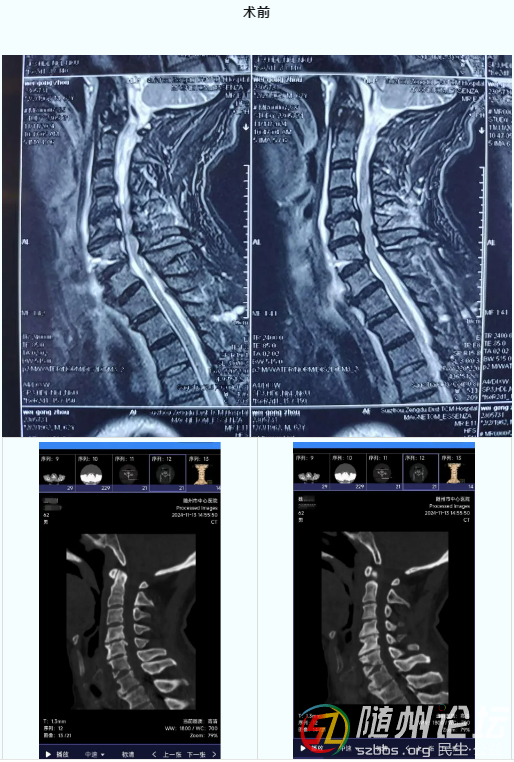

近日,隨州市中心醫(yī)院創(chuàng)傷中心以專業(yè)的醫(yī)術(shù)和高效的團隊協(xié)作,成功完成一例復(fù)雜的頸椎骨折前路固定+后路單開門減壓手術(shù),彰顯了醫(yī)院技術(shù)的硬實力。 事發(fā)當日,魏先生因突發(fā)車禍,導致全身多處損傷,四肢麻木無力, ...